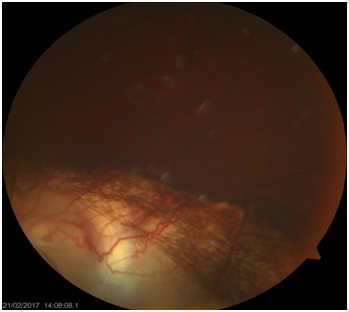

Type 7—coloboma involving only the periphery (Figure 1).

Figure 1 The course of Retinal blood vessels on choroidal coloboma changed than normal pattern in the lower part of the fundus.

It is reported that the both retinal and choroidal vessels patterns are directly affected by the size and area of the coloboma (Figure 2).13